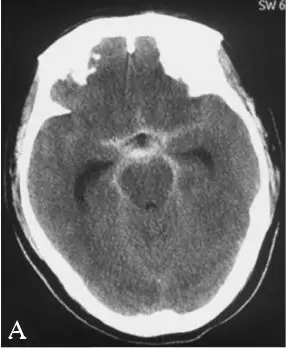

CT:头颅CT提示蛛网膜下腔出血,鞍上池为主,左侧略多,并可见四脑室内积血,无脑积水,Fisher分级4级(图18-3A)。

DSA:急诊行全脑血管造影提示基底动脉下段可见1枚形态不规则囊性动脉瘤(图18-3B)。三维重建后提示基底动脉下段开窗畸形,动脉瘤瘤颈位于开窗近段分叉处,瘤顶有子囊(图18-3C),动脉瘤瘤颈1.85 mm,瘤深5.45 mm,瘤宽2.77 mm。左侧椎动脉造影提示左侧椎动脉仅供血小脑后下动脉(PICA)区域,未汇入基底动脉(图18-3D)。颈内动脉造影未见明显异常。

A:急诊头颅CT提示弥漫性蛛网膜下腔出血及四脑室积血;

B:右侧椎动脉造影示基底动脉下段可见1枚形态不规则囊性动脉瘤;

C:右侧椎动脉造影及3D重建见基底动脉下段开窗畸形并开窗近段分叉处动脉瘤;

D:左侧椎动脉造影提示左侧椎动脉发育不良,仅供血小脑后下动脉(PICA)区域。

图18-3患者术前头颅CT及DSA影像